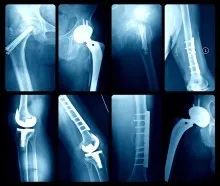

生物材料是那些與體內(nèi)組織,器官相互作用的材料。生物材料最近引起了很多關(guān)注,因?yàn)樗趯?duì)細(xì)胞、組織和器官進(jìn)行診斷治療、替換修復(fù)或誘導(dǎo)再生等領(lǐng)域有著廣泛的應(yīng)用。目前生物材料已廣泛用于牙科、心血管、美容和骨科等。而XPS在探索這類新型設(shè)備和界面的局限性和可能性方面特別有用。